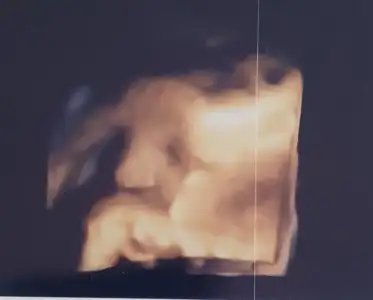

Kızlar benim de bugün kontrolum vardı cok iyi geldi minigimi görmek :) 34+3 deyiz 2.5 kg 47 cm görünüyor cok sukur hersey yolunda, eli hep agzindaydi yüzünü tam göremedik. Doktorum nst ye 36 dan itibaren başlayacağız suan gerek görmüyorum dedi ağrı sanci vs olmadığı için. 37 ye kadar çalışacağım için tahmini sezaryen ne zaman olur diye konustum sonuna kadar bekleme taraftariyim 39 u bekleriz dedi cok mutlu oldum. 36 ve 38 haftalik olunca tekrar gideceğim 38de son duruma göre doğum tarihi belirleyeceğiz. Son zamanlarda kasiklarimda baskı hissettiğimi soyledim sezaryen dikisime doğru kafası geldiği için normal dedi. Buarada son 2 haftada kilo almamışım ona da çok sevindim :)

Maşallah canım çok tatlı duruyor, kesin parmağını emiyordur. Benimkide son gittiğimde eliyle gözlerini kapatıyordu😅